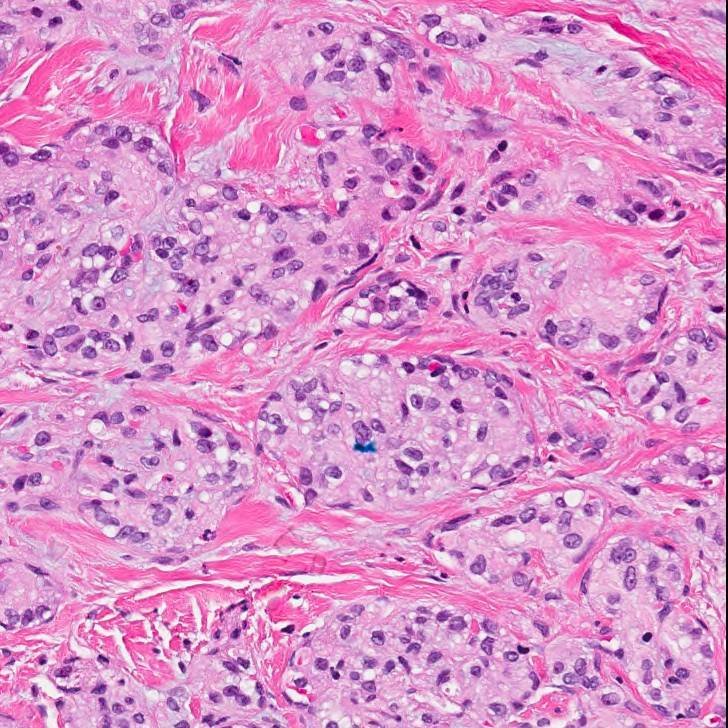

More from the non neoplastic bone marrow fascicle (arppress.org/books/book/71): Pelger-Huët syndrome (or anomaly) is due to mutations in the laminin beta receptor gene, which results in an abnormal nuclear morphology of segmented neutrophils (incidence of approximately 1 in 10,000 individuals). #HemePath